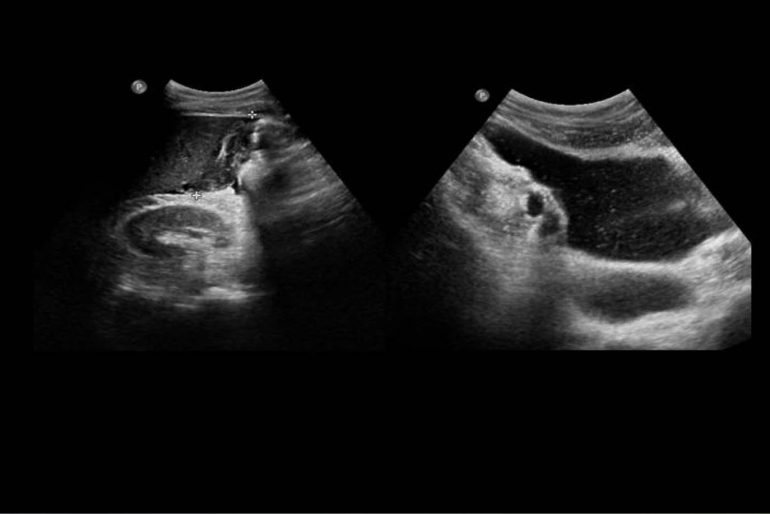

La colecistostomía percutánea se refiere al drenaje de la vesícula biliar a través de un tubo pequeño que pasa por la pared del abdomen. Se realiza con la ayuda de imágenes radiológicas, generalmente el ultrasonido, para confirmar la posición adecuada del tubo. Por lo general, se reserva la colecistostomía para la gente con colecistitis aguda o colangitis que no tolerará una cirugía abdominal.[22] Las ventajas de la colecistostomía para estos pacientes incluyen: no requiere anestesia general, puede realizarse al lado de la cama, el procedimiento es rápido, tiene una tasa de éxito superior al 95%, y la tasa de complicaciones es baja. Además, después de tratar la enfermedad aguda con la colecistostomía percutánea, se puede realizar una colecistectomía electiva.[22]